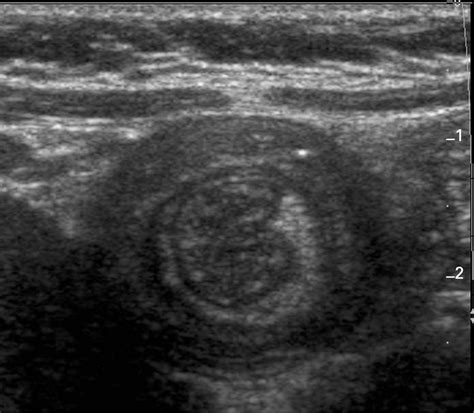

During an ultrasound examination, a transducer is placed on the abdomen. The transducer emits sound waves that penetrate the body and bounce back, creating echoes. These echoes are then converted into images that can be viewed on a monitor. The ultrasound technician or radiologist can identify the characteristic "target" or "doughnut" sign, which is indicative of intussusception. This sign appears as concentric rings of alternating hypoechoic and hyperechoic layers, representing the layers of the intussuscepted bowel.

Interpreting the results of an ultrasound of intussusception requires a trained eye. The characteristic signs of intussusception include:

• Target sign: This appears as concentric rings of alternating hypoechoic and hyperechoic layers, representing the layers of the intussuscepted bowel.

• Pseudo-kidney sign: This sign is seen when the intussuscepted bowel appears as a mass with a hypoechoic center and a hyperechoic periphery, resembling a kidney.

• Crescent-in-doughnut sign: This sign is seen when the intussuscepted bowel appears as a crescent-shaped mass within a doughnut-shaped mass.

These signs, along with the clinical presentation, help healthcare professionals confirm the diagnosis of intussusception.